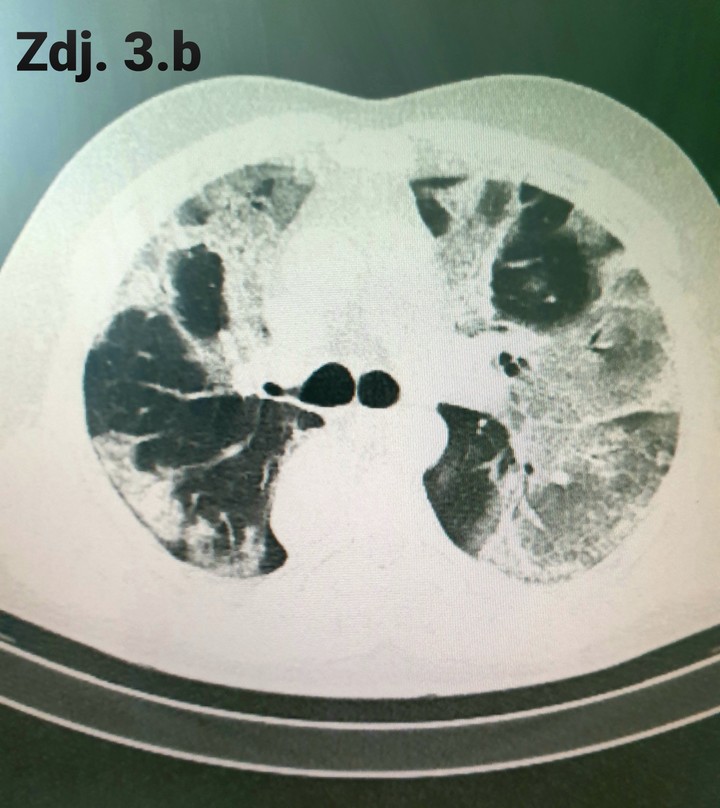

Na zdjęciu nr 3 a i b widzimy przekrój przez klatkę piersiową, uzyskany za pomocą tej metody obrazowania. Zdjęcia pokazują zakres zmian śródmiąższowych, czyli te wszystkie białe jakby rozlane plamy u jednego pacjenta. Oceniamy je na różnych wysokościach płuc, tutaj na zdjęciu 3a na wysokości szczytów płuc (tuż poniżej ramion) i na poziomie serca (zdj. 3b). Procentowa zawartość zdrowego (czarnego) miąższu jest niewielka. Oczywiście w większości przypadków zmiany w toku leczenia zmniejszają się, a obraz płuc ulega uporządkowaniu, ale ten proces wymaga czasu. Ile? Na tą chwilę, nie mamy jeszcze długoterminowych, opartych na dużej liczbie przypadków badań, które pokazałyby, jak długo i w jakim stopniu organizm będzie wracał do pierwotnego stanu i czy w ogóle wróci.

Zdjęcie 3a

Zdjęcie 3b